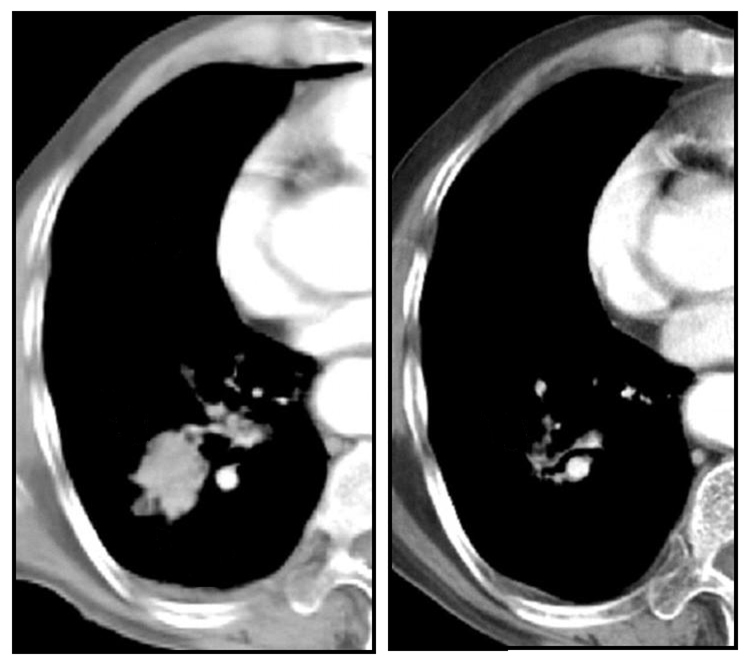

Figure 5

Chest CT of a patient treated with RFA- before and after treatment.

The advantages of bronchoscopic RFA are the non-surgical treatment as well as shorter hospital stay. Even though the size of destroyed tissue is small, CT-bronchoscopic guided RFA has the potency as a therapeutic tool, especially for local control in medically inoperable patients. Surgery ± chemo-radiotherapy is the treatment of choice for stage I and II NSCLC, offering the best chance of cure [35]. For medically inoperable patients, however, stereotactic radiotherapy [36] and percutaneous RFA [31, 32, 37] have been shown to be effective (fig. 5). Whether bronchoscopic RFA can serve as an alternative tool, needs further exploration.